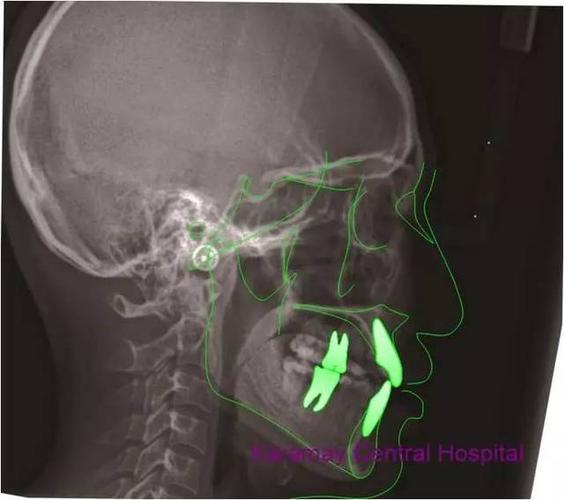

头侧位片显示患者牙合型为安氏Ⅱ类,轻度骨性Ⅲ类,上前牙唇倾,均角.

治疗后头颅侧位片